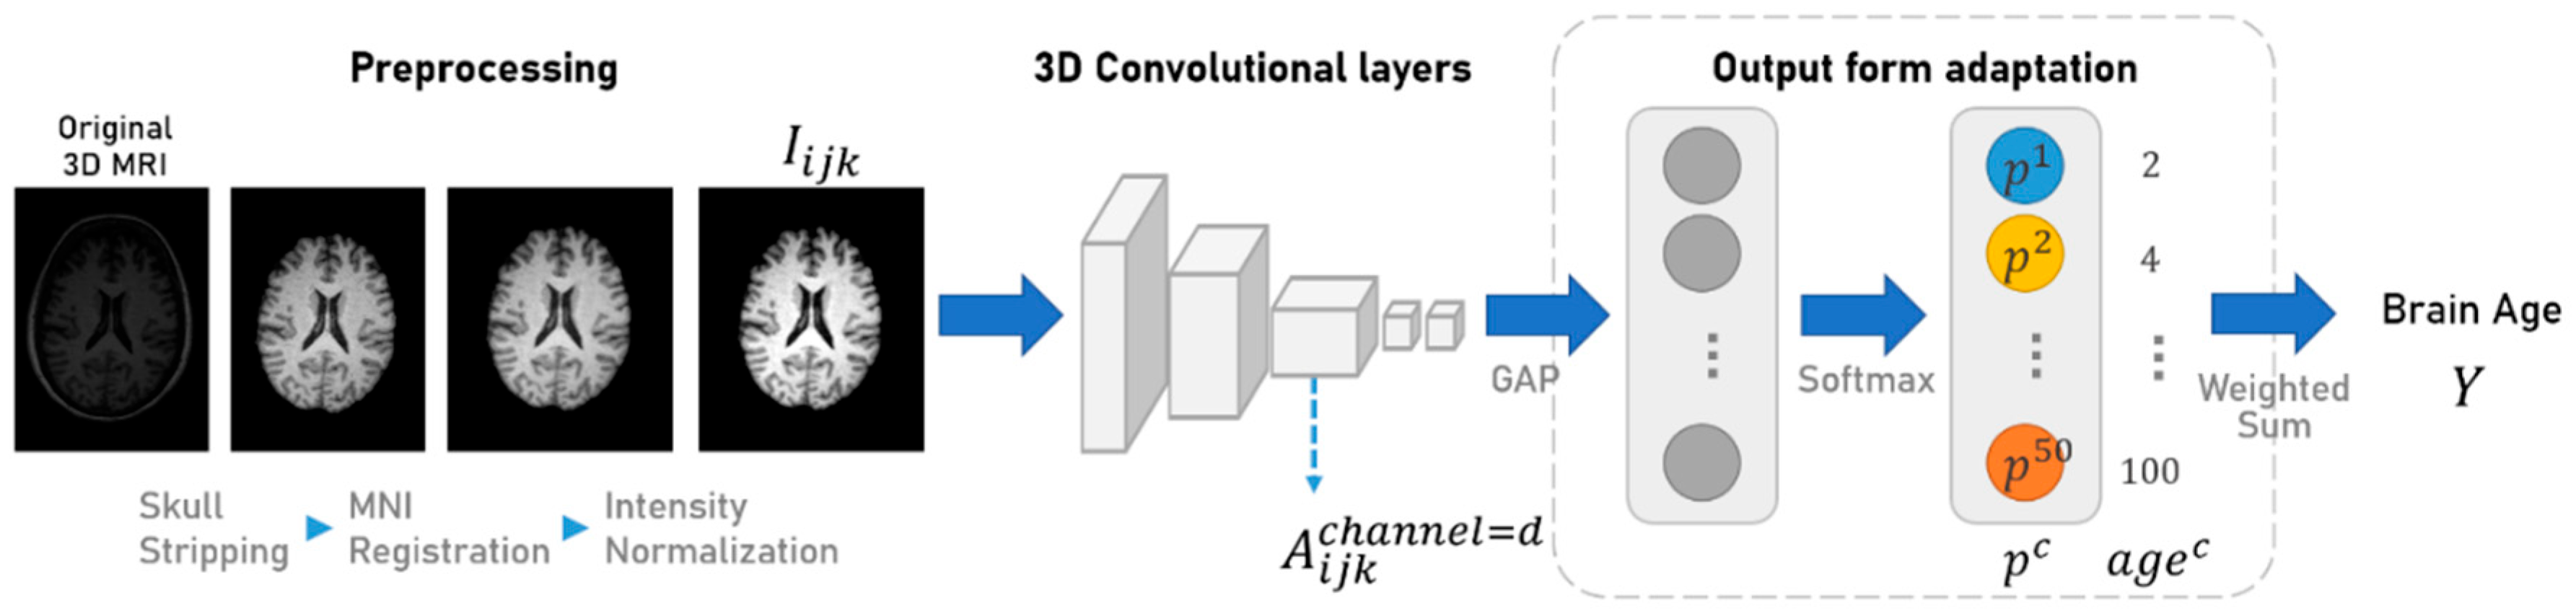

3.3. Model Architecture Design

3.4. Softmax-Derived Brain Age Mapping